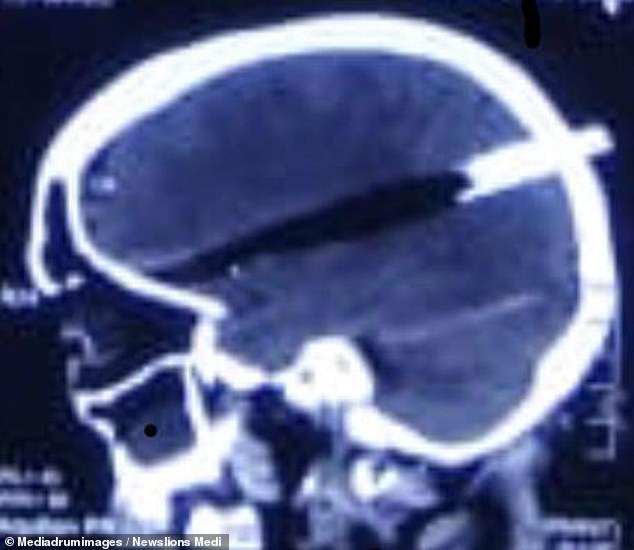

・インドのムンバイで女性がキッチンですっ転んだ

・運悪く熱々の圧力鍋の蓋が頭に突き刺さった

・手術して元気になった